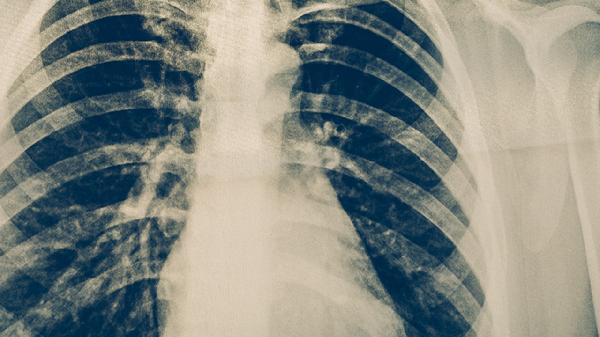

肺结核病人在家可通过隔离防护、规范用药、营养支持、环境消毒、症状监测等方式护理。肺结核是由结核分枝杆菌引起的慢性传染病,需长期规范治疗。

护理期间家属需佩戴N95口罩,接触患者前后规范洗手。保持患者情绪稳定,避免过度劳累。定期复查胸部CT和痰菌检测,直至医生确认治愈。康复期仍须继续营养补充,逐步恢复适度运动如散步、太极拳等,增强免疫力预防复发。